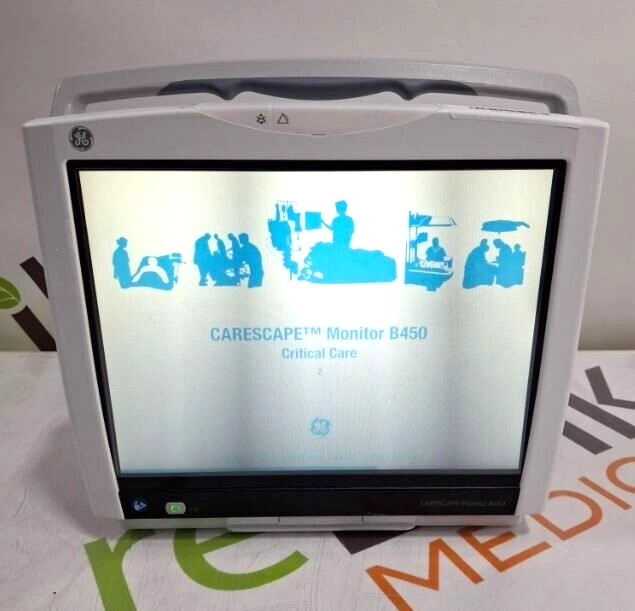

GE Healthcare Carescape B450 Patient Monitor

$618.00

USD

GE Healthcare Carescape B450 Patient Monitor

$618.00

USD